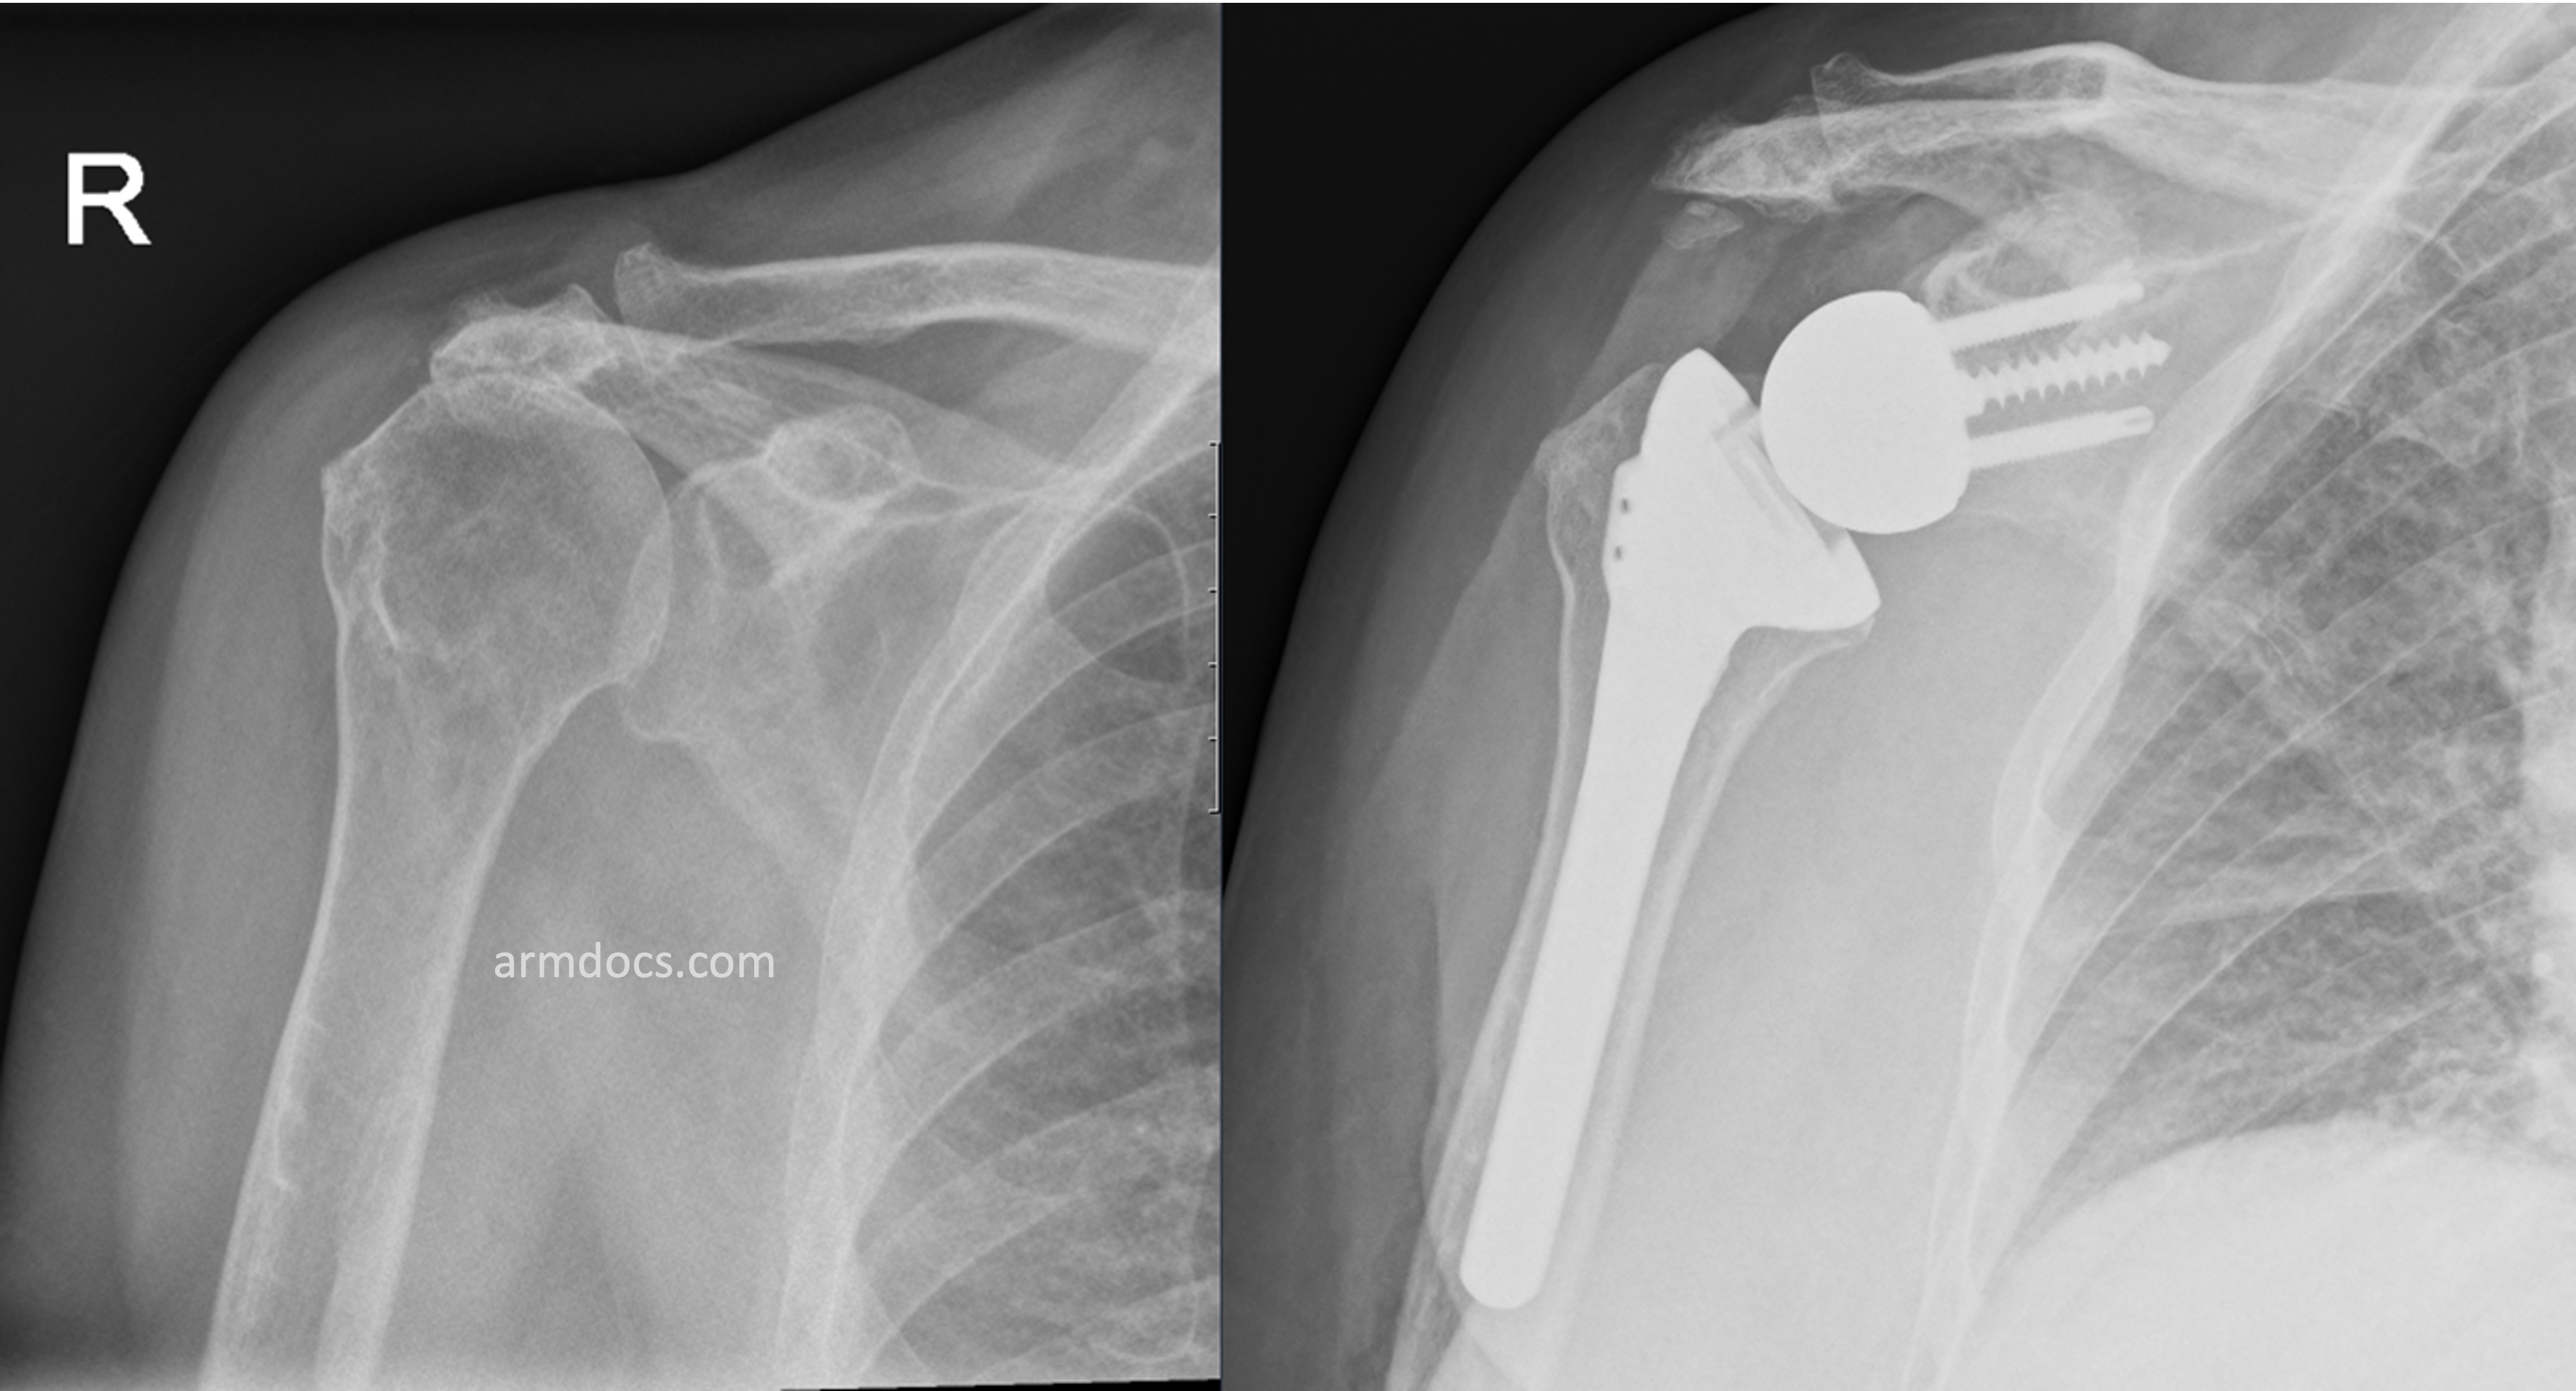

The procedure is performed under a combination of general and regional anaesthesia. The shoulder joint is exposed. The bones on either side of the joint are prepared, a metal “ball” is fixed to the native socket with screws and a “socket” on a stem is fixed to the humerus, usually with bone cement.